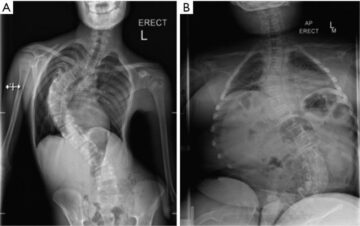

ما الأمراض العصبية التي تسبب اعوجاج العمود الفقري؟ يعاني بعض الأطفال والمراهقين من اعوجاج العمود الفقري (Scoliosis) نتيجة أسباب غير مجهولة، لكن في كثير من الحالات يكون السبب مرتبطًا باضطرابات عصبية تؤثر على العضلات